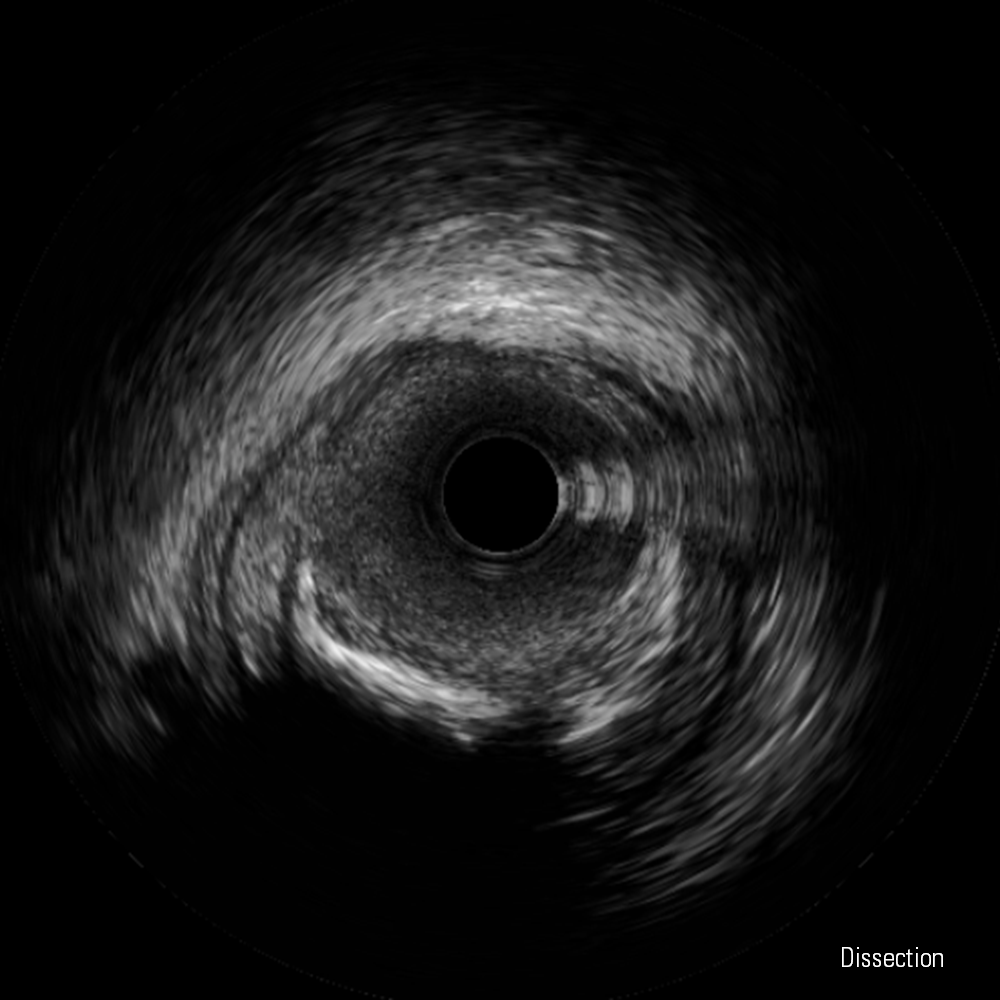

Dissection, False Lumen and Thrombus images courtesy of Boston Scientific.